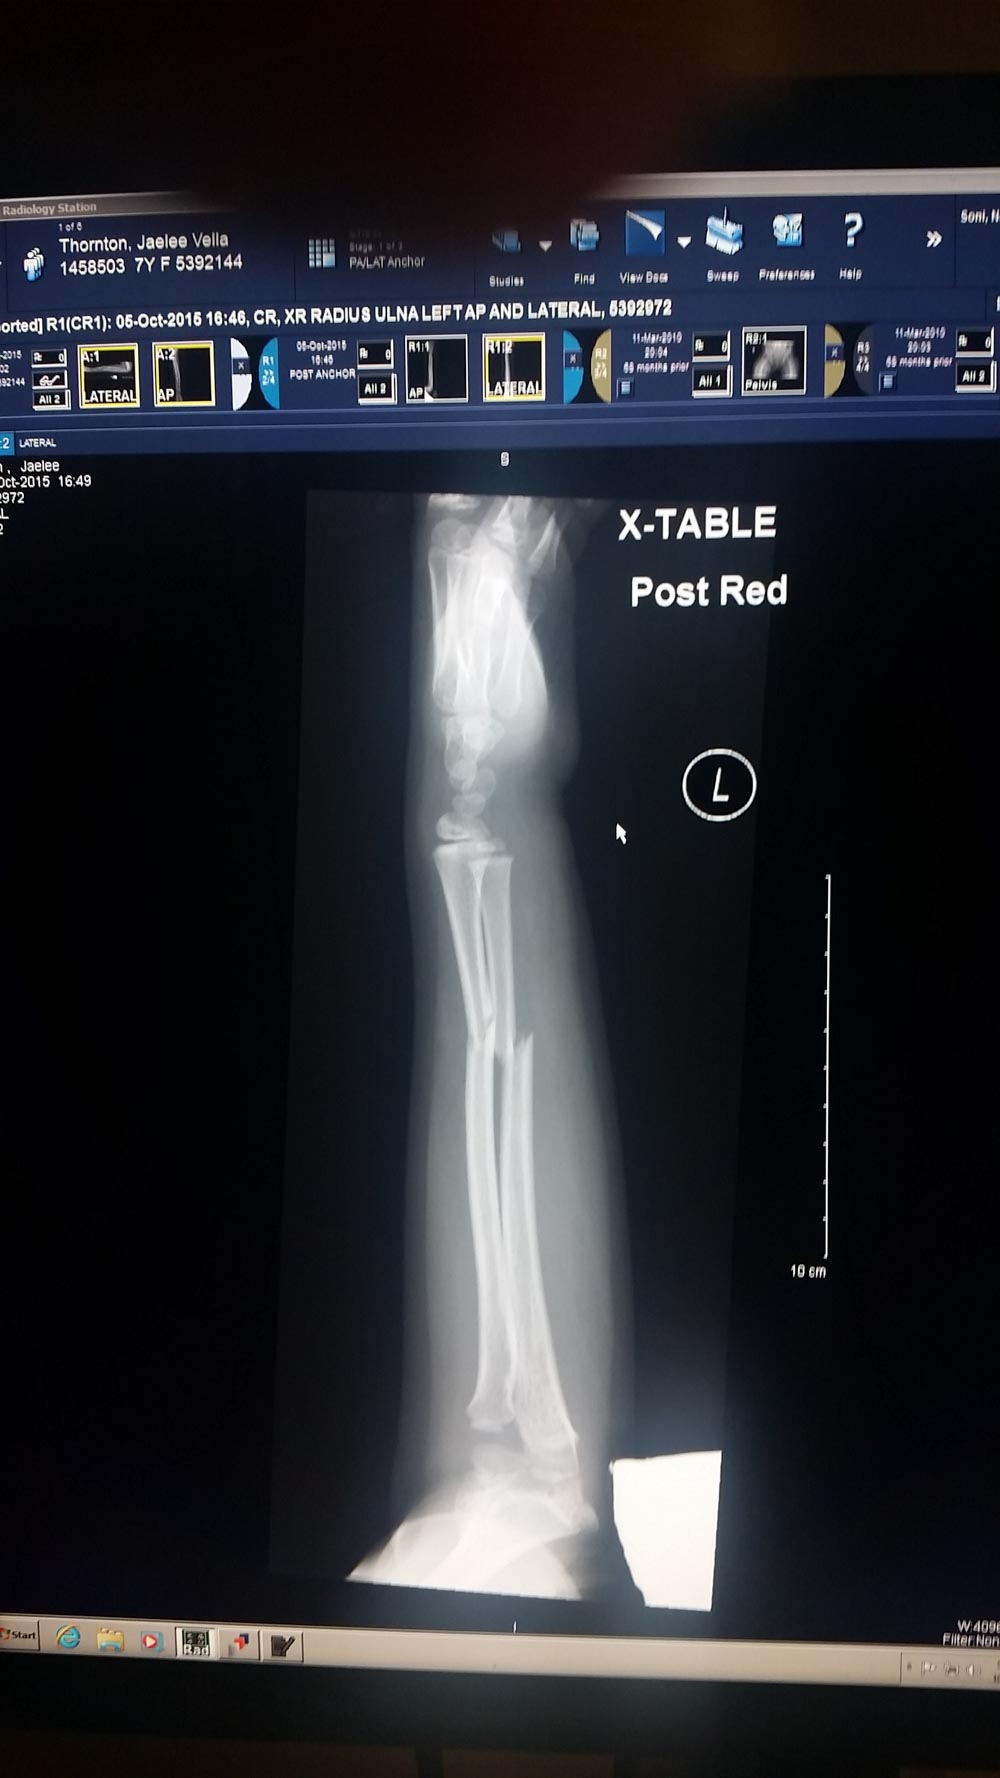

At the ER they put us back into a room right away. From there however it took forever. We ended up being their for 6 hours. She had multiple x-rays, they reset her arm and finally put a splint on it. It turns out she broke both bones in her arm and the doctor was concerned she may need surgery. We are still not sure if she’ll need surgery or not. The orthopedic doctor says it looks pretty good but we wont know for sure until she gets her cast off in 3 weeks. It has been quite an experience.